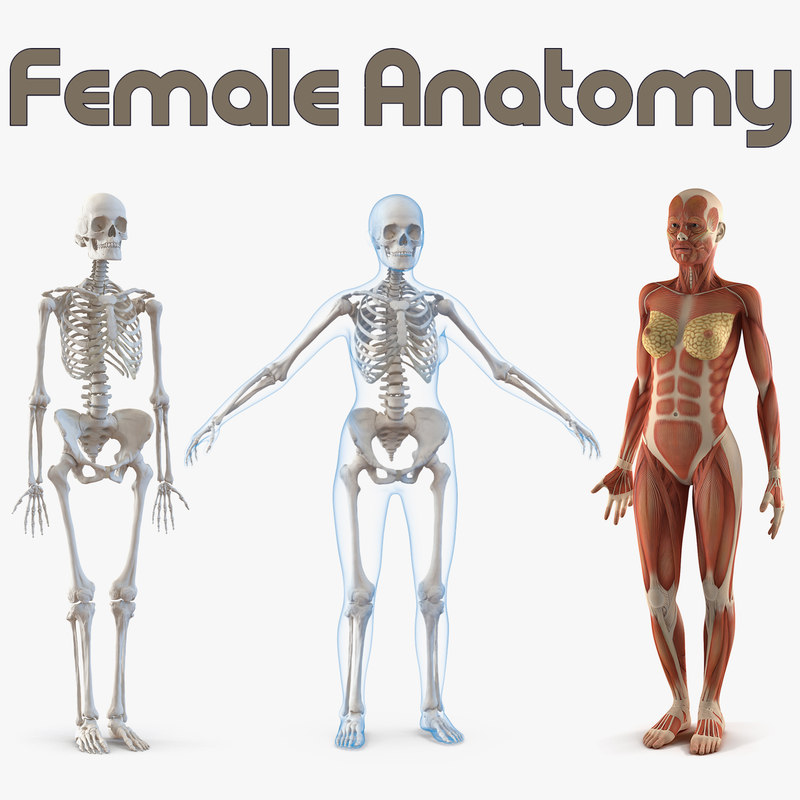

Female Anatomy Body